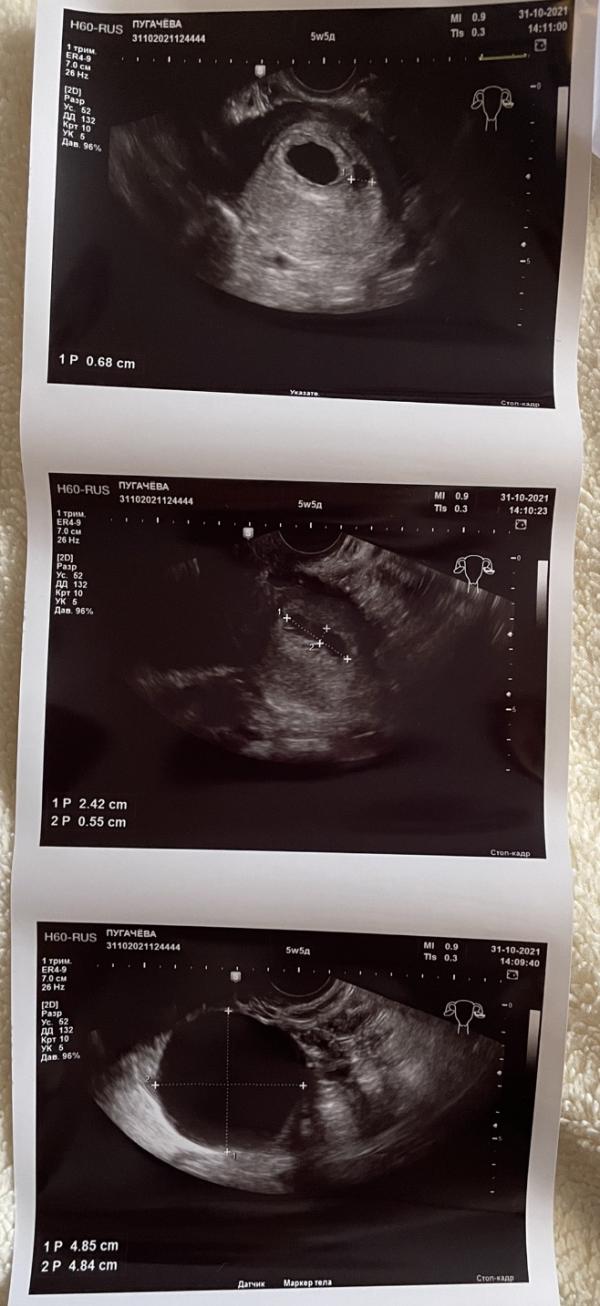

Итак, 31 октября 5 недель 5 дней:

Размер плодного яйца 16мм, КТР 5мм, желточный мешок до 3мм, сердцебиение до 106 уд/мин ! 😳 (по сердцебиению сказали вообще 6 недель 1 день, как так то 🤷🏻♀️ может ранняя овуляция все таки?), я не ожидала услышать ❤️ так рано 😁

И, не ожидала услышать, что у меня - ❗️ретрохориальная гематома 24x6x7 мм.. (не кровит) это маленькая или большая считается?

И киста выросла, по сравнению с предыдущим узи. Ещё и болит((

Ещё узист странный попался, снимок с плодом пришлось просить распечатать дополнительно, так как сначала распечатал он снимки только «проблемных» мест 🤦🏻♀️